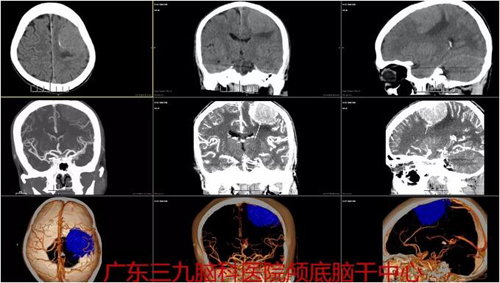

图1:术前CTA示左侧顶部占位性病变内示多发小血管影